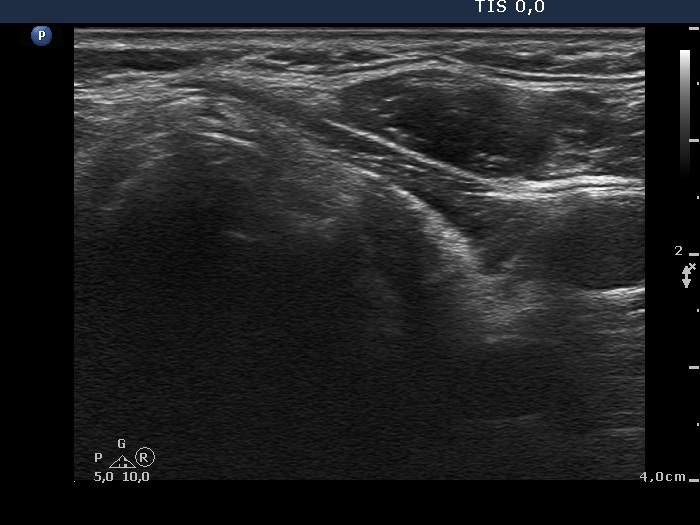

Discrete lesion or nodule in Hashimoto's thyroiditis - case 15 (714) (ultrasonographic picture 7)

Left lobe, transverse scan. Great proportion of this lobe is hypoechogenic, only a thin echonormal rim can be observed.